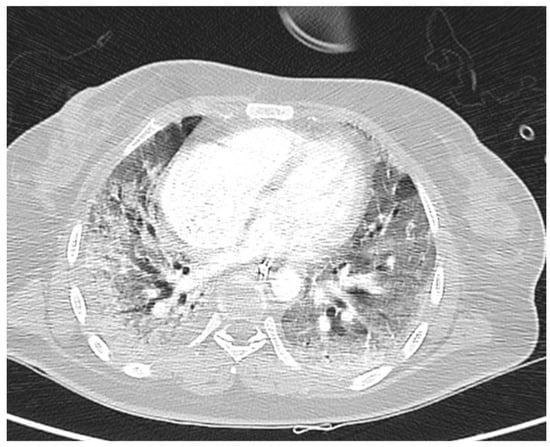

- Zilioli, V.R.; Albano, D.; Arcari, A.; Merli, F.; Coppola, A.; Besutti, G.; Marcheselli, L.; Gramegna, D.; Muzi, C.; Manicone, M.; et al. Clinical and prognostic role of sarcopenia in elderly patients with classical Hodgkin lymphoma: A multicentre experience. J. Cachexia Sarcopenia Muscle 2021, 12, 1042–1055. [Google Scholar] [CrossRef]